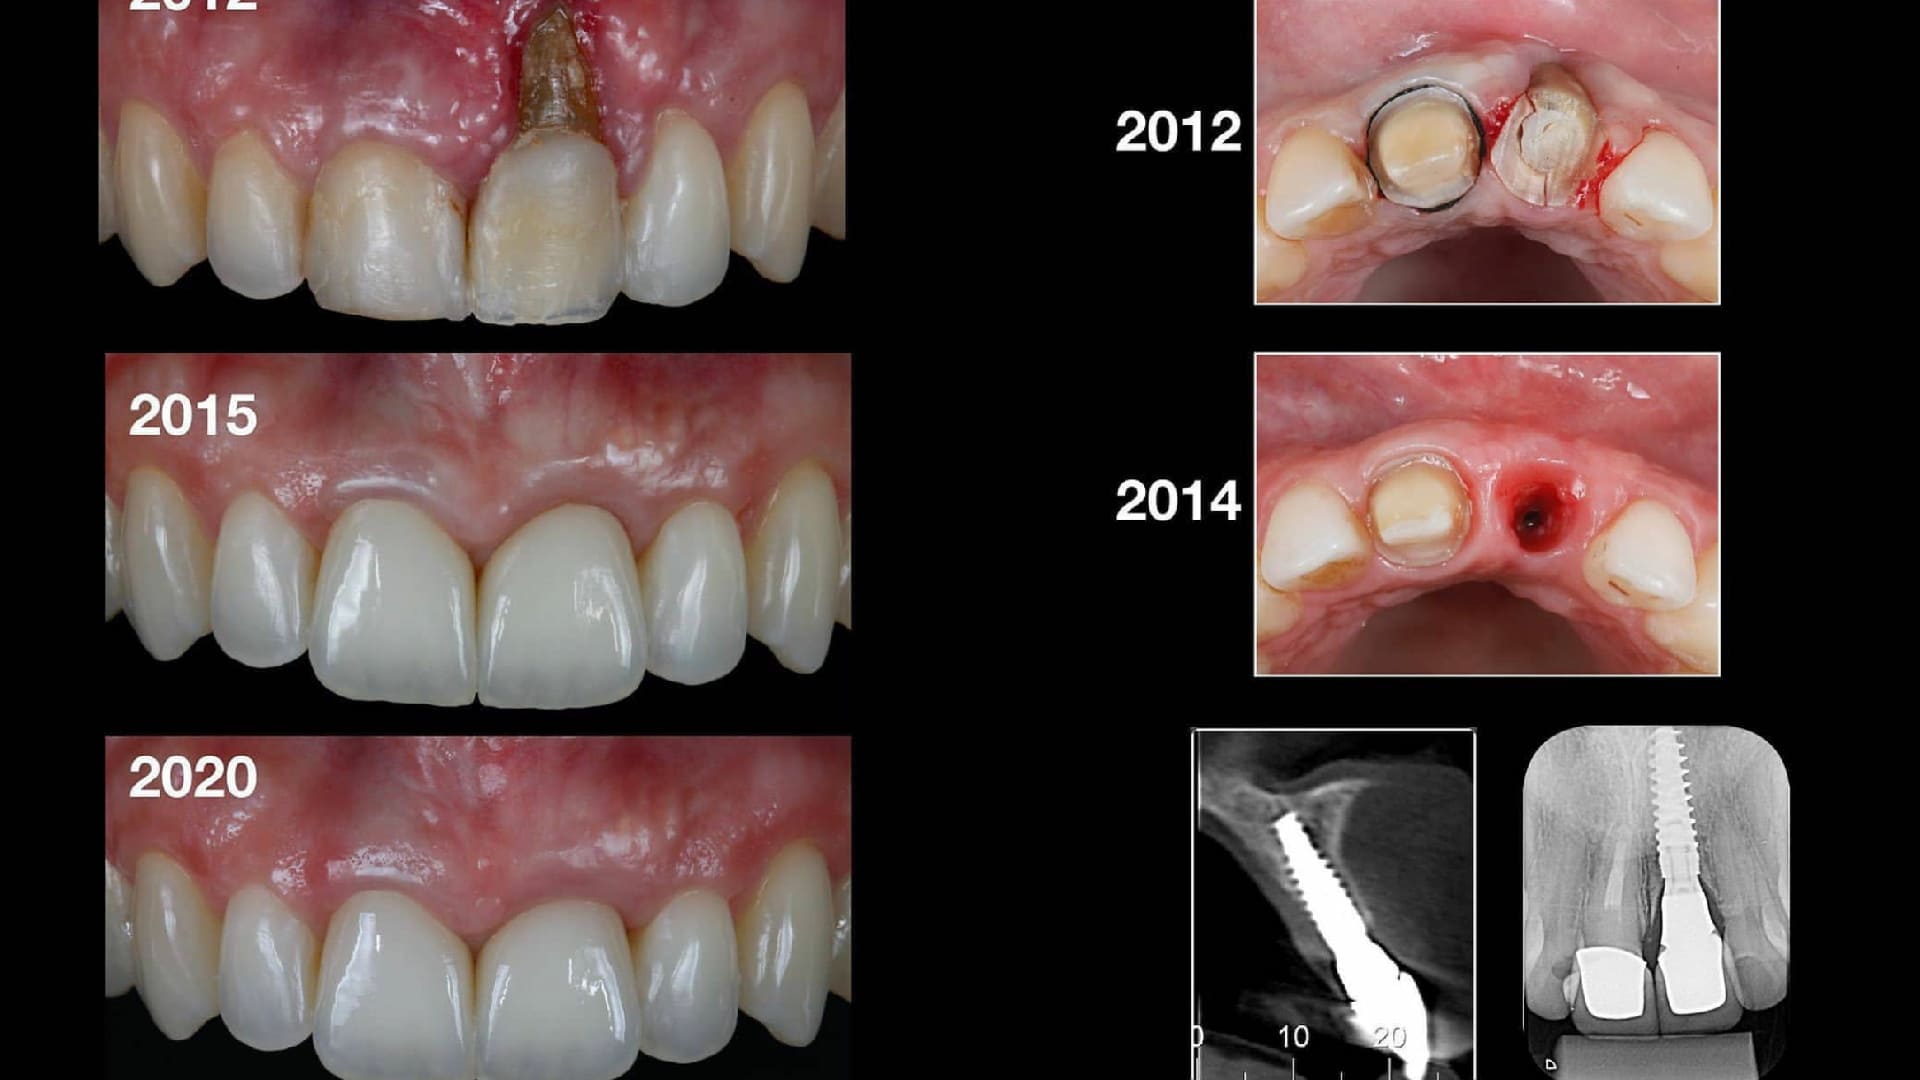

CLINICAL CASES